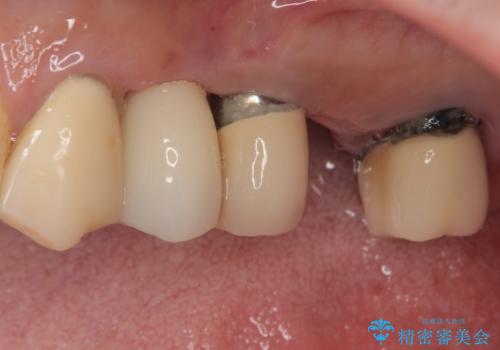

クラウンを装着できないため、プラスチックを歯に流し込んで仮歯のようにしている状態でした。

プラスチックを外すと同時に抜歯を行い、1ヶ月ほど待機して歯肉が落ち着いたことを確認してから速やかにインプラントを埋入することとしました。